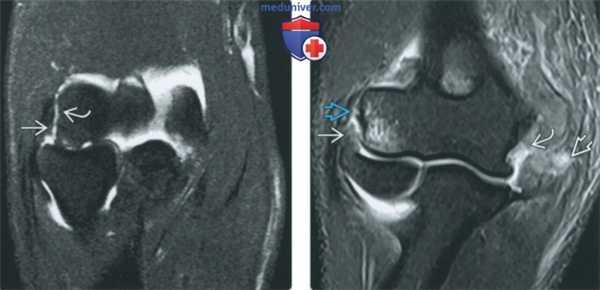

(Слева) МР-артрография в режиме Т2ВИ FSE FS, сагиттальный срез: визуализируются «целующиеся» ушибы передней поверхности головки лучевой кости и задней поверхности головки мыщелка плечевой кости, обусловленные перенесенным ранее задним вывихом головки лучевой кости. В этом случае отличить травматический дефект головки мыщелка плечевой кости от псевдодефекта позволяет наличие отека костного мозга.

(Справа) МР-артрография в режиме Т2ВИ FSE FS, коронарный срез, этот же пациент: отмечаются дефект хряща, импрессия субхондрального отдела кости и перифокальный отек костного мозга.